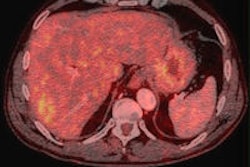

PET & PET/CT examinations per million population in 2010

Source: Development of PET in Western Europe, Anthony Stevens, PhD, EANM 2011.Average patient throughput per scanner rose from 651 in 2002 to 1,559 in 2010. Throughput ranged from 864 in Germany to 2,228 in France. The maximum throughput achieved was estimated at 13.2 patients per day, or 3,168 patients per year. At centers operating between 2004 and 2010, average patient throughput by an average of 12.4% a year, rising from 1,168 to 2,360. The levels of investigation were 1.39 per million of population in the north of Europe, 3.28 in the south of Europe, and 1.84 in the west of Europe (the Netherlands, Belgium, Germany, Switzerland, and Austria).